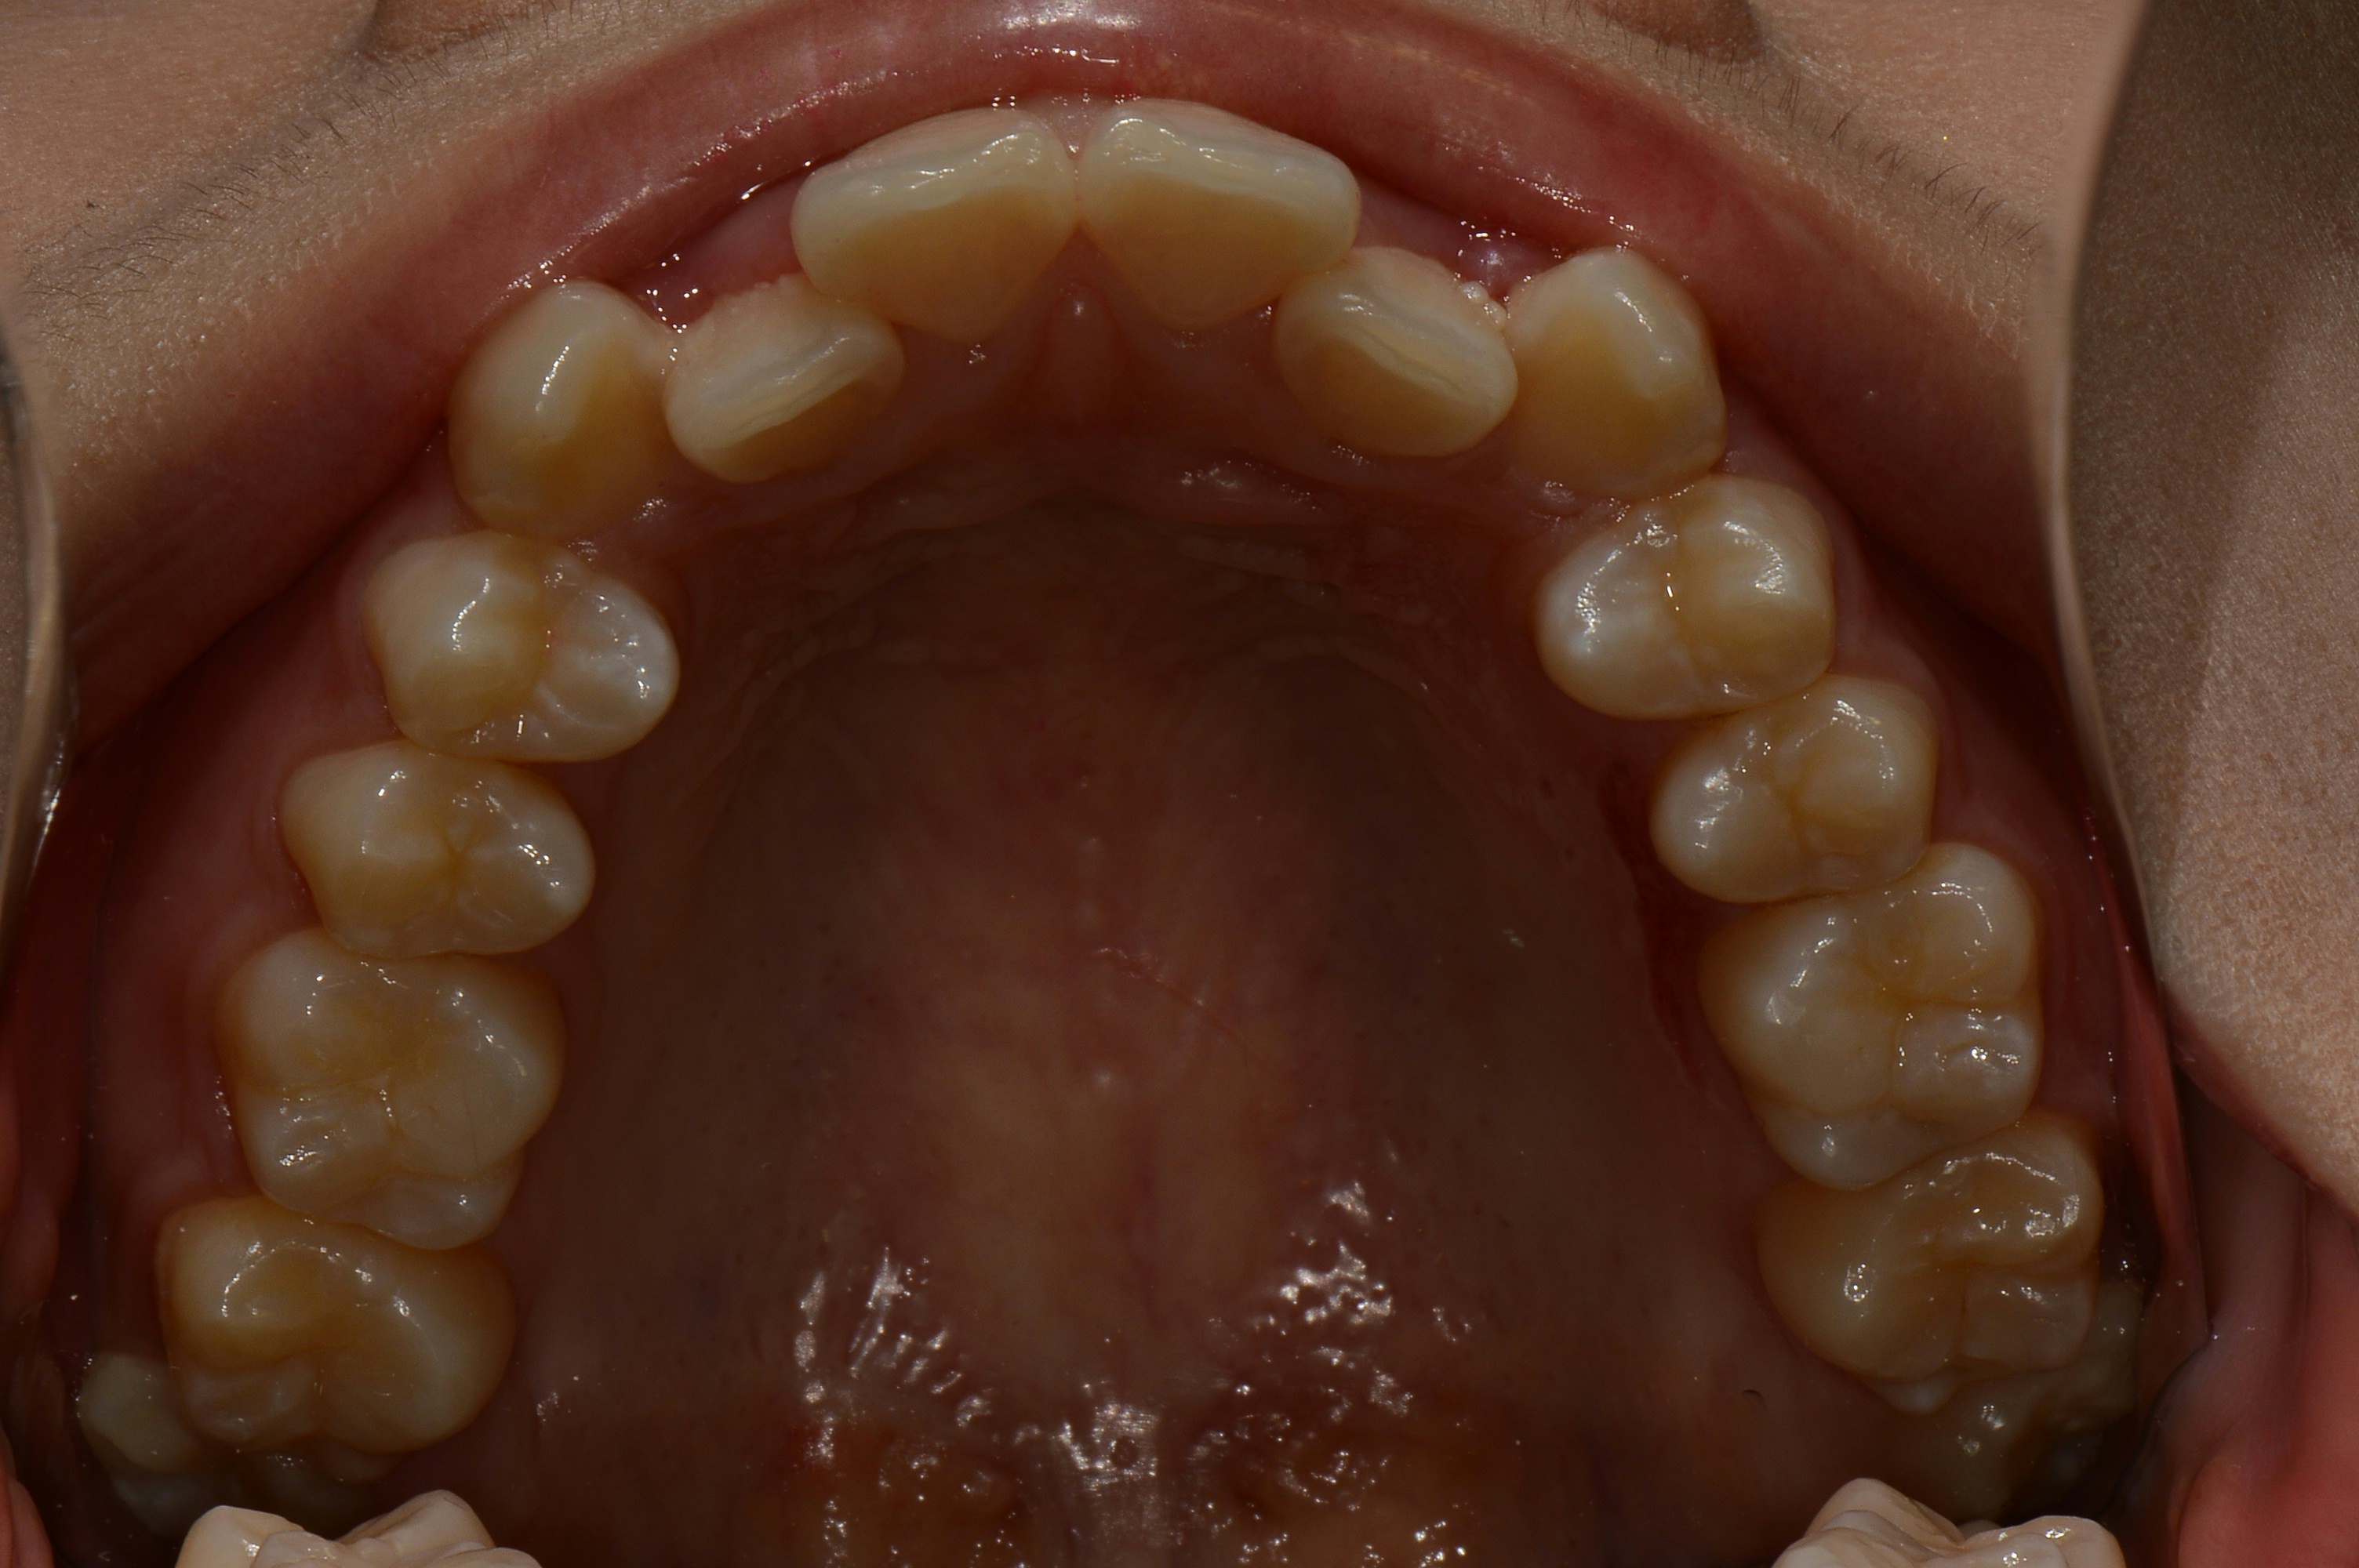

치료 후 사진입니다.